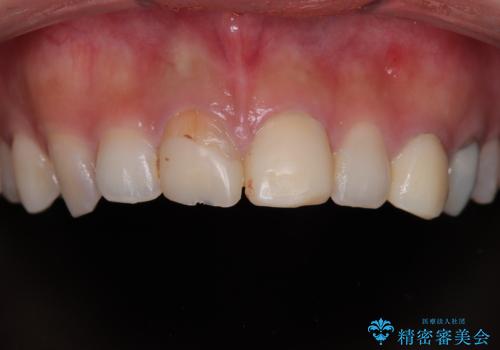

- 20代女性の患者様。

他院にて「上の前歯(右上中切歯)は抜歯してインプラントかブリッジにする必要がある」と診断され、大変ショックを受けられていました。

すでに根管治療を受けた歯でしたが、急に担当医が変わり、「抜歯が必要」とだけ説明されたことに不安感を抱き、当院を受診されました。

左上中切歯と犬歯も仮歯のままで、将来への不安が大きかったご様子です。

精密検査の結果、右上中切歯には**フェルール(歯の周囲の健全な歯質)**がほぼ存在せず、このままの状態での保存は困難と判断しました。